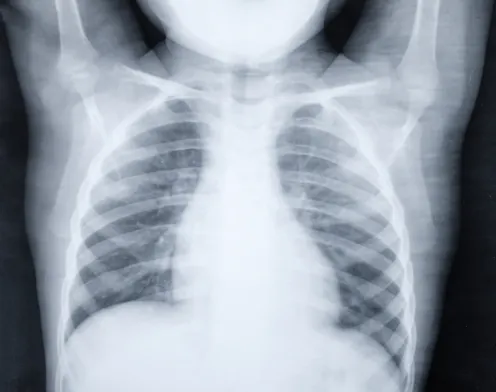

Other advances are being made to improve pneumonia diagnosis. These include improved radiological methods, point-of-care tests which are used at or near patient care to speed up diagnosis, and the use of host biomarkers that examine the type of immune response a person develops to identify the cause of infection.